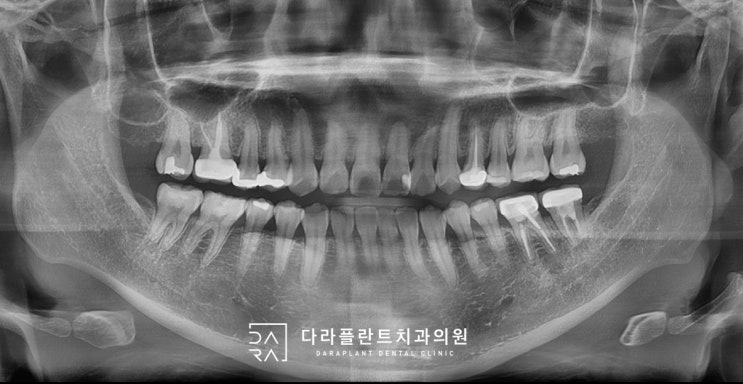

화정역 치과. 매복사랑니를 늦게 빼면 생기는 문제. 대부분의 사랑니는 빨리 뺄수록 좋습니다. 사랑니 앞 치아 충치. DME

안녕하세요 화정역 치과 다라플란트입니다. 오늘은 매복사랑니로 인한 충치 문제를 다뤄보도록 하겠습니다....